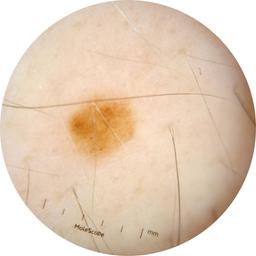

ISIC_9219276

Clinical

Field Value

acquisition_day 482

age_approx 55

anatom_site_1 Trunk

anatom_site_2 Posterior trunk

anatom_site_general posterior torso

concomitant_biopsy False

diagnosis_1 Benign

diagnosis_confirm_type single image expert consensus

family_hx_mm True

image_manipulation instrument only

image_type dermoscopic

lesion_id IL_5010026

patient_id IP_7167913

personal_hx_mm True

sex male